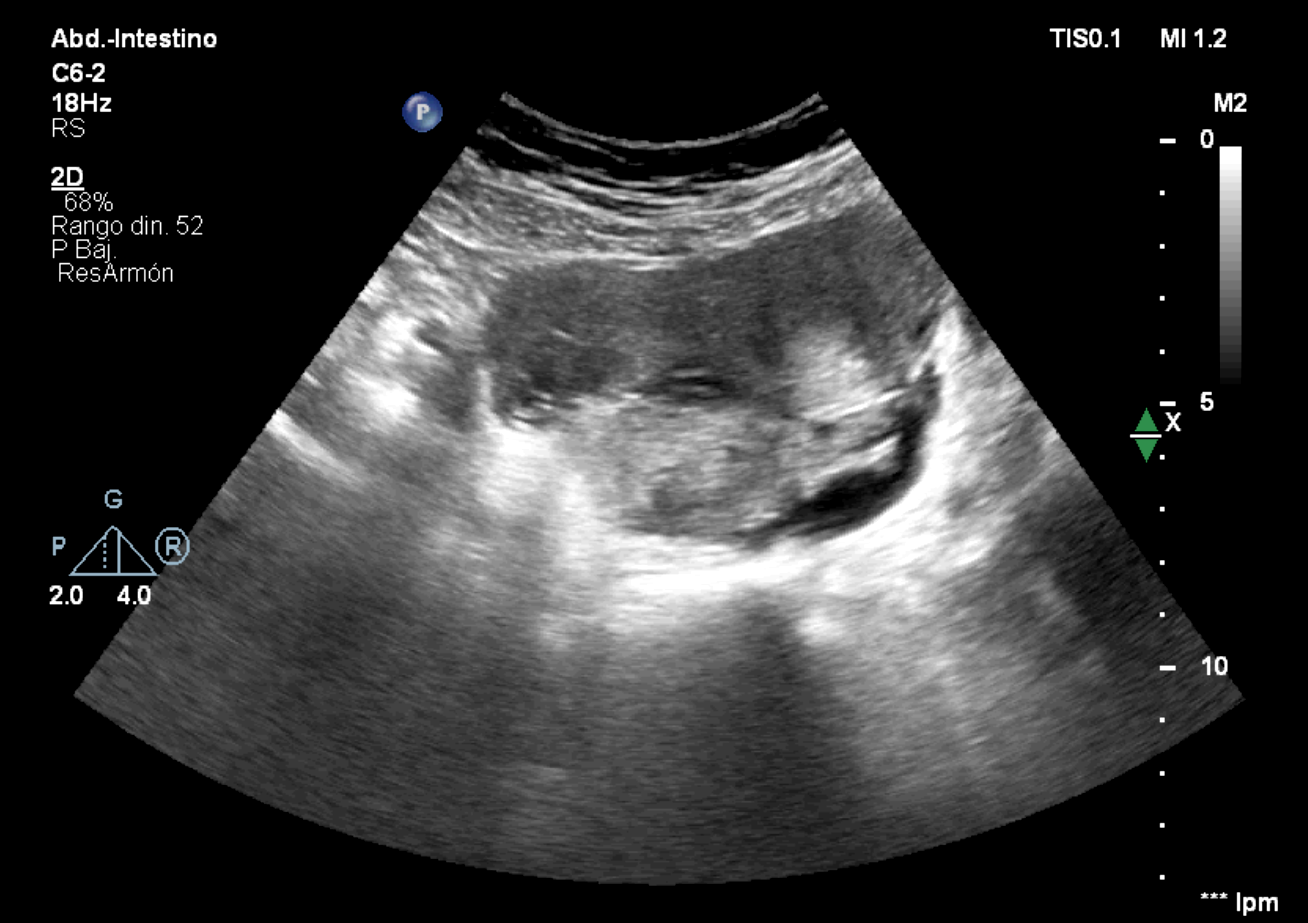

Ante la persistencia de dolor con pruebas anodinas, se realiza ecografía clínica.

Hallazgos ecográficos

En pelvis menor una estructura paranexial derecha de 76 x 36 mm, bien delimitada, y estructura tubular anecoica adyacente que parece corresponder a la trompa de Falopio dilatada.

Se contacta con Ginecología, repiten test de embarazo, positivo débil. Realizan nueva ecografía, corroborando hallazgos previos, compatibles con embarazo ectópico y hematosalpinx.